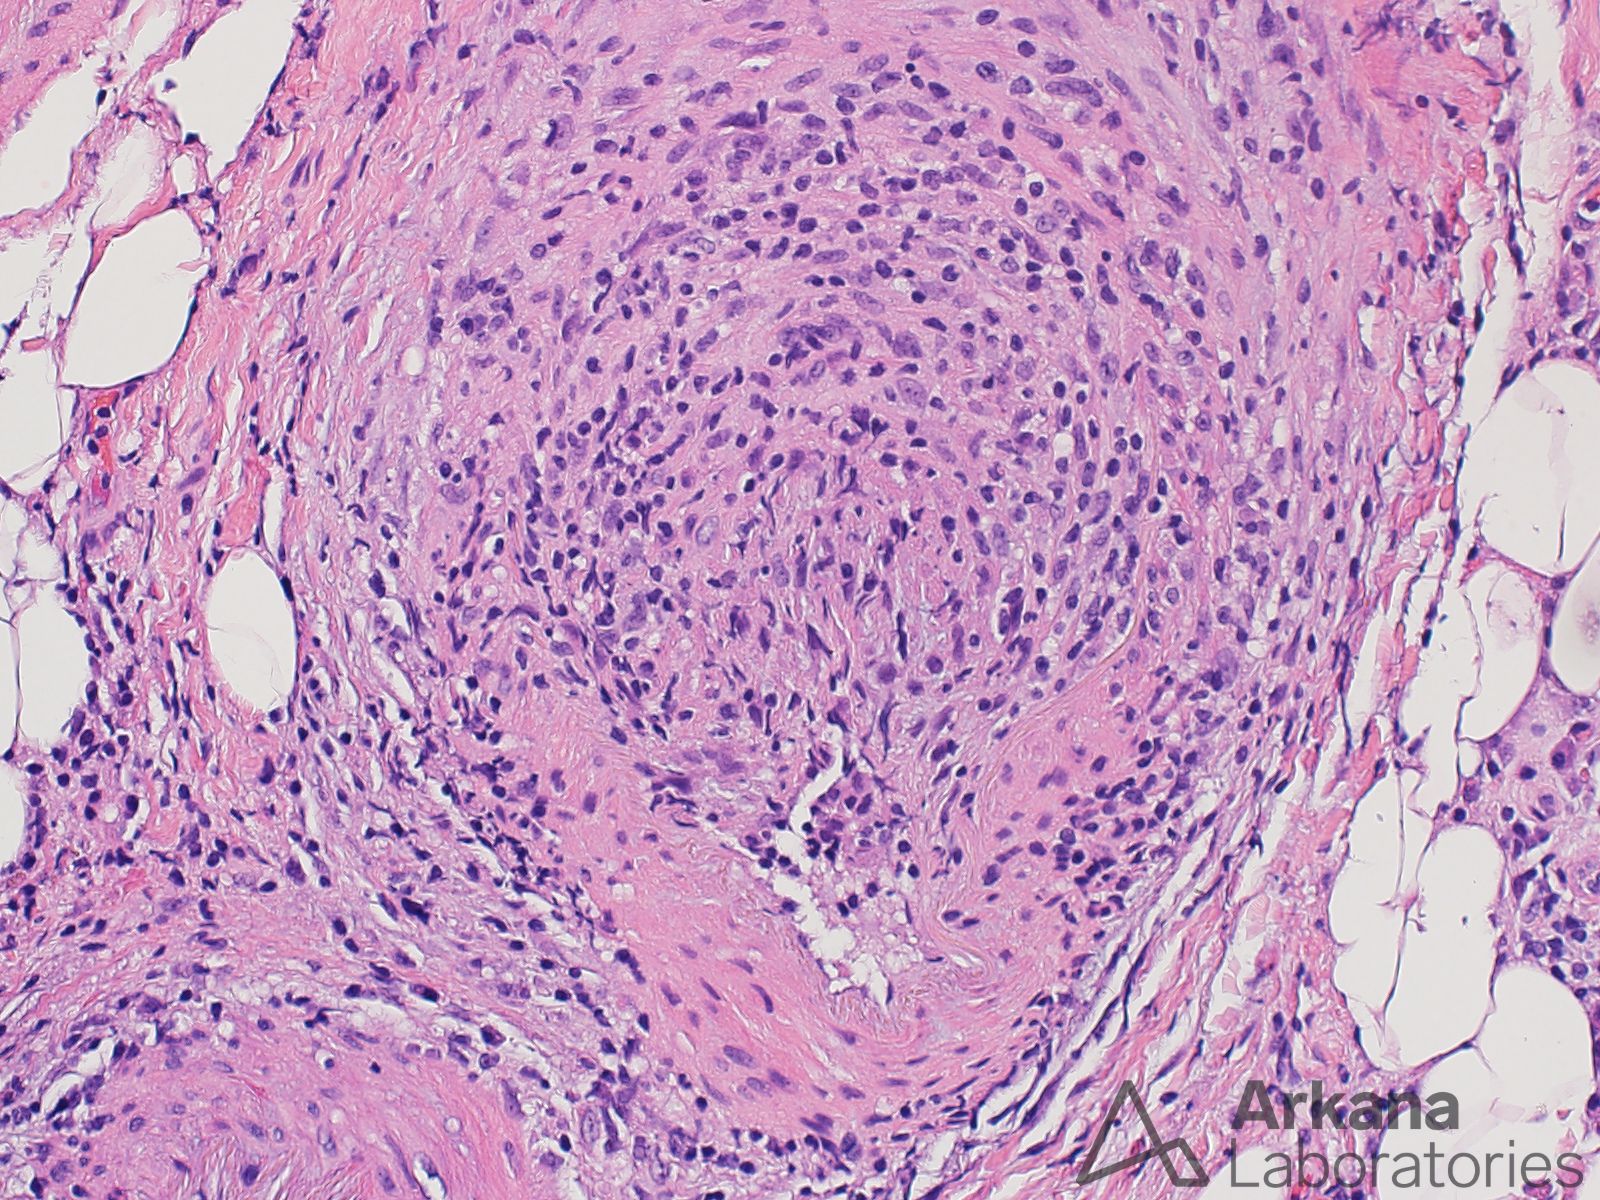

The H&E stain images demonstrate two blood vessels surrounded by chronic inflammatory cells and macrophages that also infiltrate the blood vessel walls, and areas of fibrinoid necrosis. The overall morphologic abnormalities are consistent with the presence of a small vessel vasculitis. In the context of this patient’s clinical history, vasculitis may be seen in the setting of Rheumatoid arthritis (rheumatoid vasculitis) and may also rarely be induced by leflunomide (i.e. drug induced vasculitis).

The features provided in the images are not those of polymyositis or dermatomyositis. No well-formed granulomata characteristic of sarcoidosis are seen. However, the granulomata of sarcoidosis may involve blood vessels (so-called sarcoid vasculopathy).